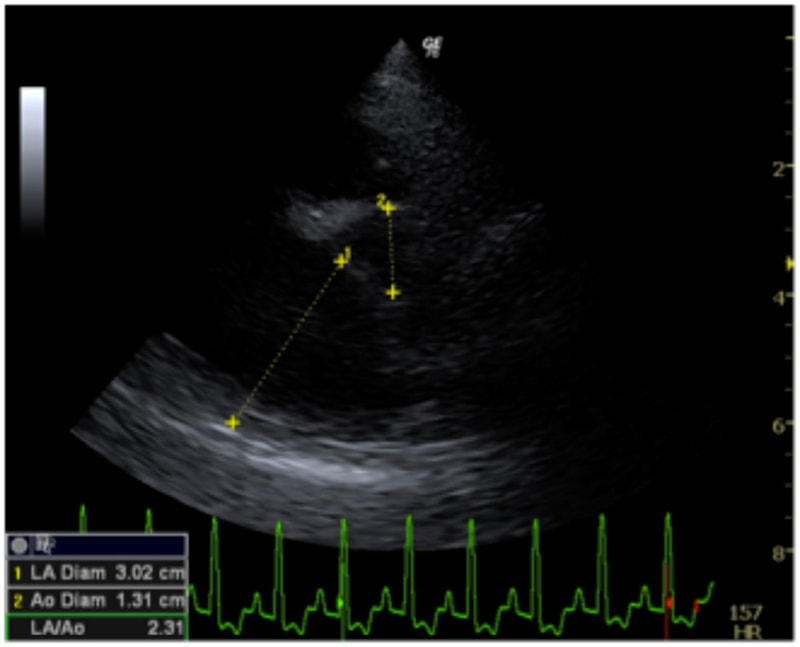

症例6:【ACVIM StageD ビーグル 10歳 去勢雄】

D:La/Ao比の重度拡大あり

左側胸壁心尖部領域を最強点とするLevine 5/6の収縮期性心雑音が聴取された。安静時にも咳が認められる。胸部レントゲン検査において重度の心拡大が及び肺水腫が認められた。超音波検査では、重度の僧帽弁閉鎖不全、三尖弁閉鎖不全が認められた。三尖弁逆流速度から肺高血圧症が示唆された。ACE阻害薬、ピモベンダン、硝酸イソソルビド徐放剤、ベラプロストナトリウム、利尿剤としてフロセミド及びスピロノラクトンを用いて治療を行っている。